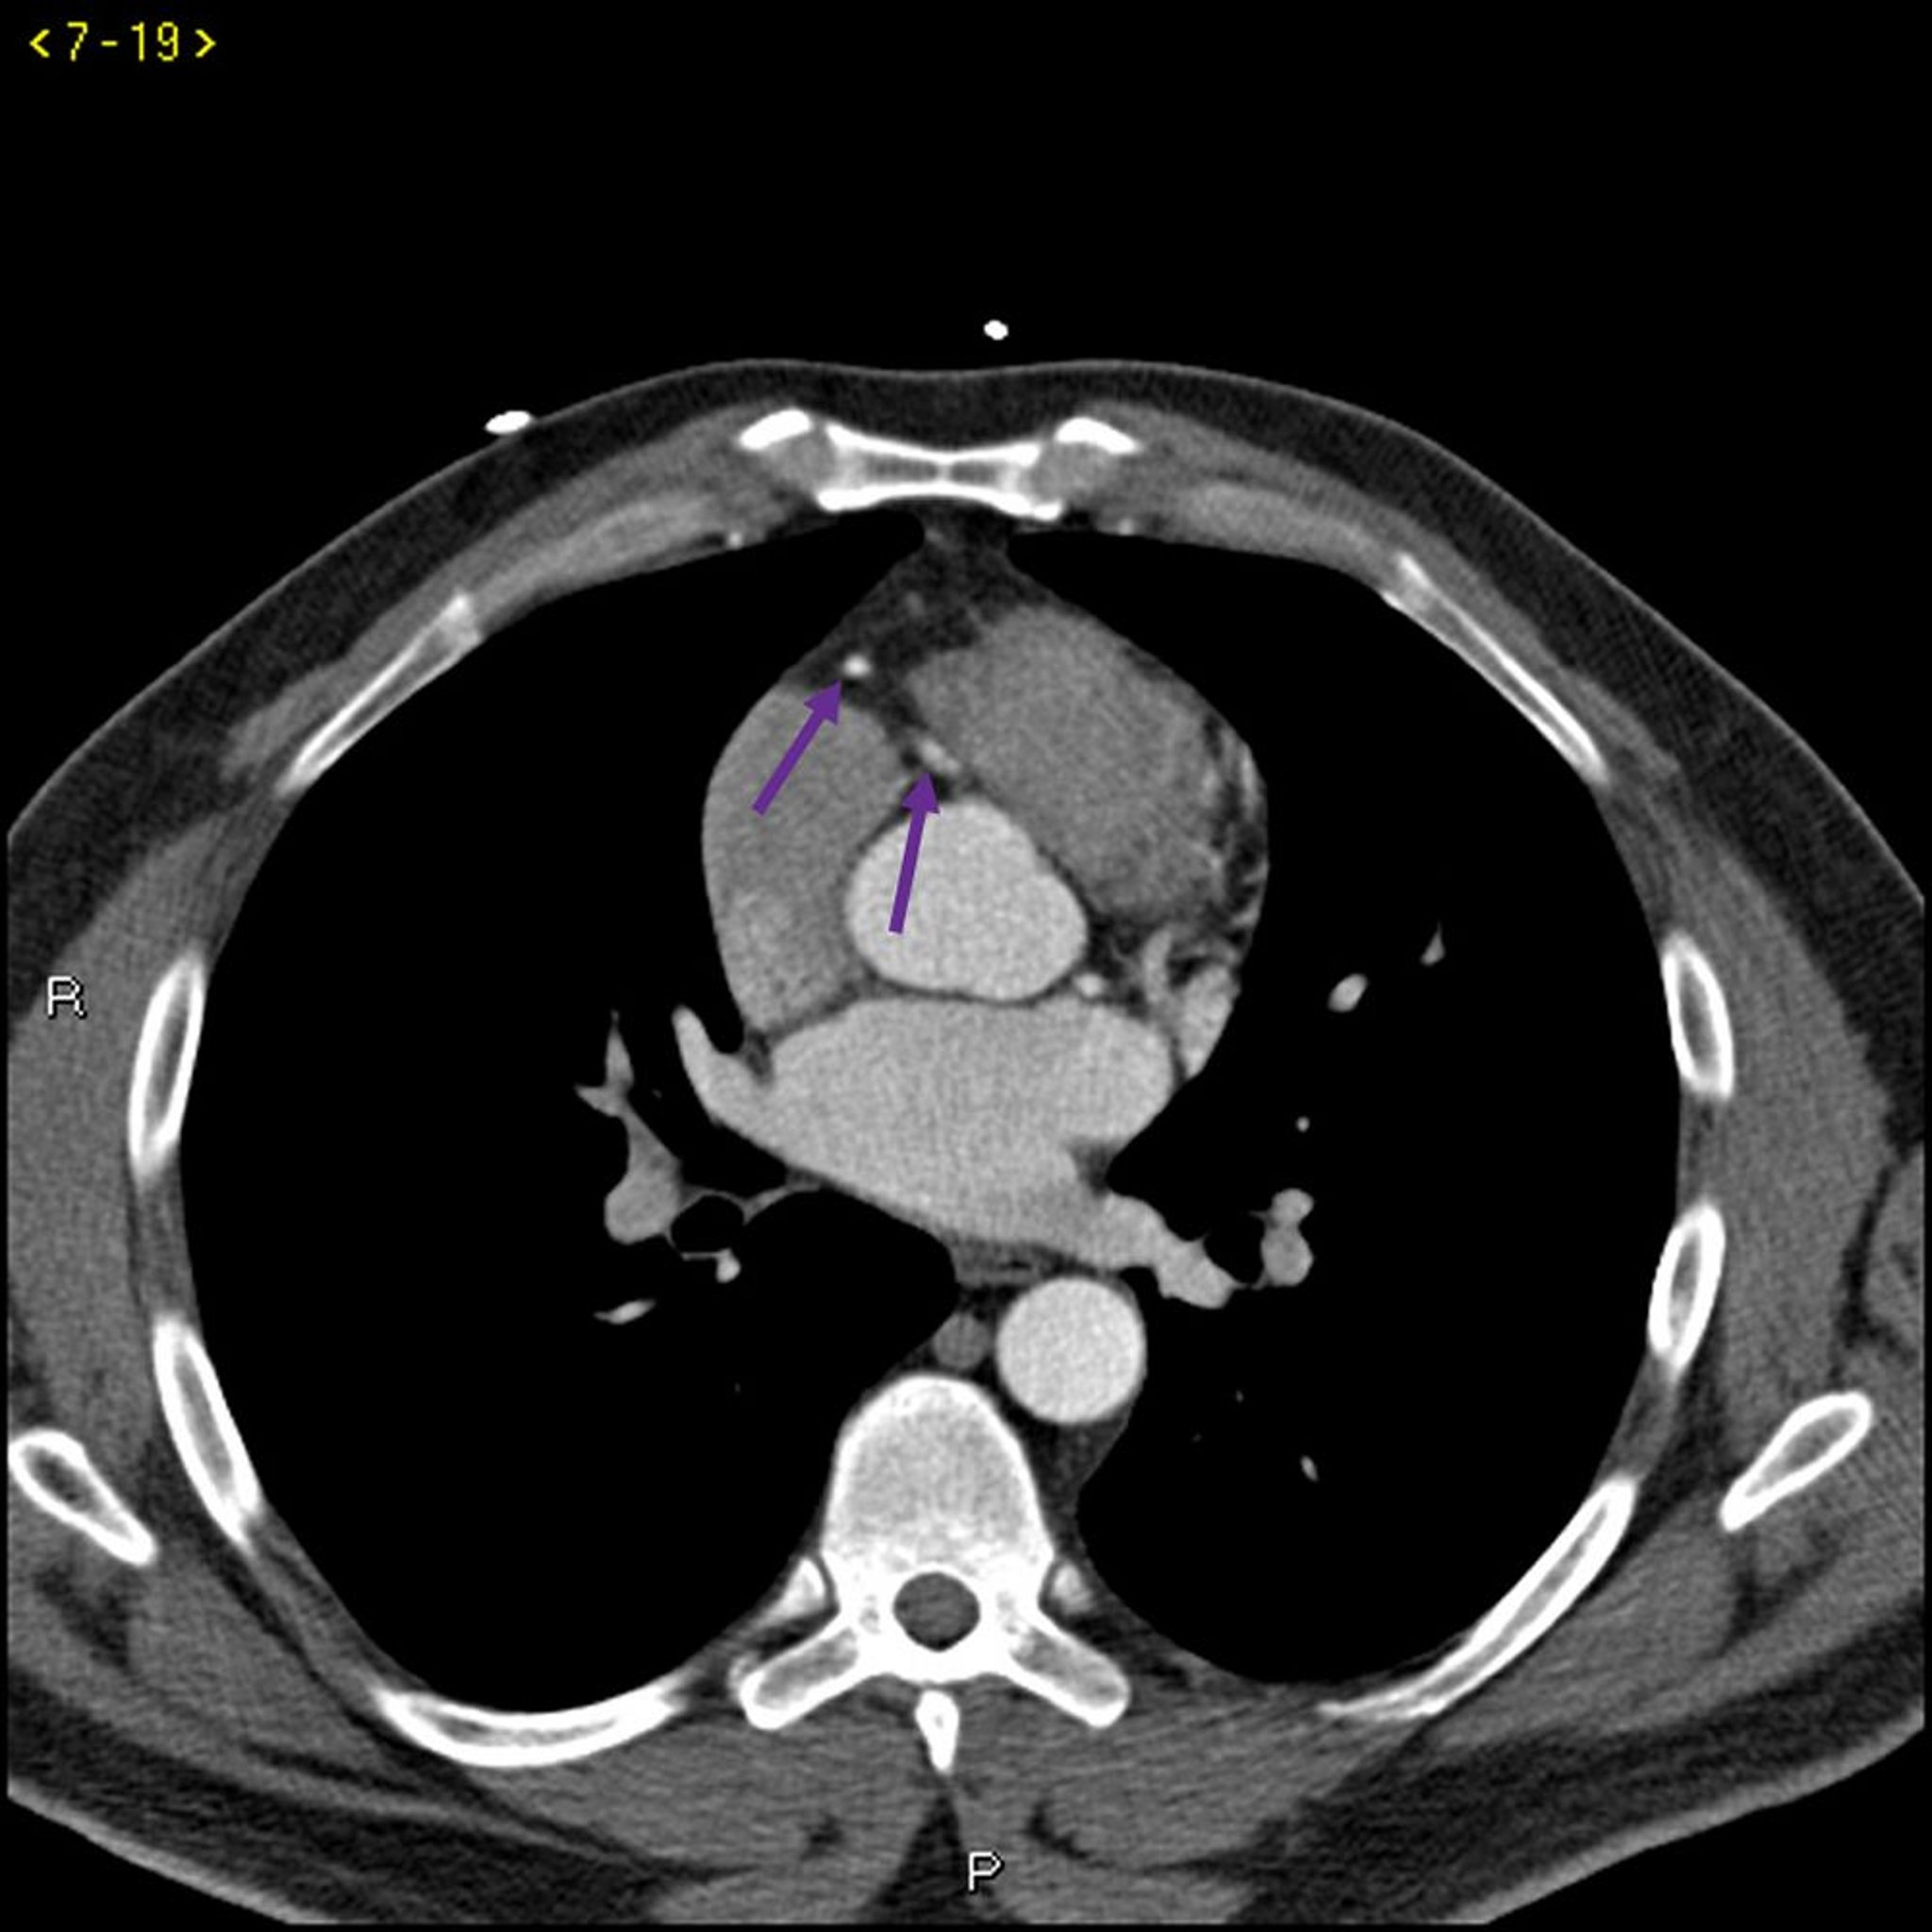

КТ с контрастированием, показывающая коронарные артерии в норме – слайд 4

КТ с контрастированием, показывающая коронарные артерии в норме Левая ветвь коронарной артерии обозначена красной стрелкой. Левая передняя нисходящая и левая огибающая артерии обозначены зеленой и синей стрелками соответственно, а правая коронарная артерия – филетовой стрелкой.